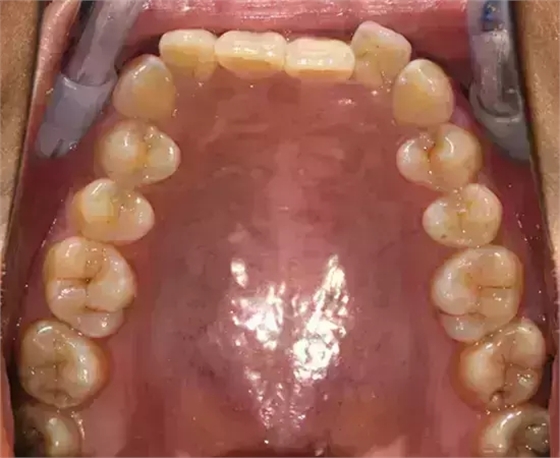

患者側(cè)面凸,鼻唇角較銳,笑時(shí)露齦笑明顯上下牙列擁擠,磨牙尖牙Ⅱ 類關(guān)系,3 度的深覆牙合,上頜中切牙伸長內(nèi)傾拔除上頜雙側(cè)的第一前磨牙,先粘上頜高轉(zhuǎn)矩的自鎖托槽排齊牙列,唇向開展上頜切牙,有一定的覆蓋,粘下頜標(biāo)準(zhǔn)轉(zhuǎn)矩托槽,上頜 1, 2 之間植入種植支抗壓入,同時(shí)后牙 5, 6 之間植入種植支抗內(nèi)收前牙,打開咬合關(guān)閉間隙。治療關(guān)鍵:前牙轉(zhuǎn)矩的控制第 1 個(gè)月 上頜粘上 Damon Q 高轉(zhuǎn)矩托槽,上 .014 熱激活 NiTi 絲。第 3 個(gè)月 上換 .014 x .025 熱激活 NiTi 絲。第 5 個(gè)月 上頜基本排齊,覆蓋增大,上換 .017 x .025 NiTi絲,下頜粘托槽,下 .014 熱激活 NiTi 絲。第 7 個(gè)月 上 .017 x .025 NiTi 絲加搖椅,下?lián)Q .014 x .025 熱激活 NiTi 絲第 9 個(gè)月 上頜換 .019 x .025 NiTi 絲加搖椅,下頜換 .017 x .025 NiTi 絲第 11 個(gè)月 下頜換 .019 x .025 加搖椅,上頜 1, 2 之間, 5, 6 之間植入種植釘,下頜出現(xiàn)散隙。第 13 個(gè)月 上頜換 .019 x .025ss 加搖椅,前牙種植釘用 Power Chain 壓低前牙(每側(cè) 100g),后牙種植釘關(guān)閉間隙(每側(cè) 150g),下?lián)Q .019 x .025ss,Power Chain 關(guān)閉間隙。第 19 個(gè)月 上頜前牙基本壓低到位去除前牙種植釘,繼續(xù)用關(guān)閉間隙,下頜散隙關(guān)閉。

第 22 個(gè)月 上頜覆蓋變小,去除 5, 6 之間種植釘,后牙前移關(guān)閉間隙。第 30 個(gè)月 患者未配合中線牽引,下中線仍有 1mm 右偏,患者對矯治效果滿意要求拆除,拆除固定矯治器,取模制作壓模保持器。 1.骨性 Ⅱ 類的患者內(nèi)收前牙時(shí)需對上頜前牙的轉(zhuǎn)矩進(jìn)行較好的控制才能獲得良好的面型和唇部形態(tài)。 2.露齦笑的患者治療前要分析其病因是唇、牙齦、牙齒、牙槽骨、上頜骨或多種因素結(jié)合,再制定矯治方案。 3.Ⅱ 類第二分類伴露齦笑的患者的上頜前牙移動軌跡是唇向開展-壓低-整體內(nèi)收。 4.Ⅱ 類第二分類牙齒舌傾比較厲害的情況,上頜中切牙慎用樹脂咬合墊。 5.壓低前牙或控根移動時(shí)容易發(fā)生牙根的吸收,需輕力緩慢的移動。